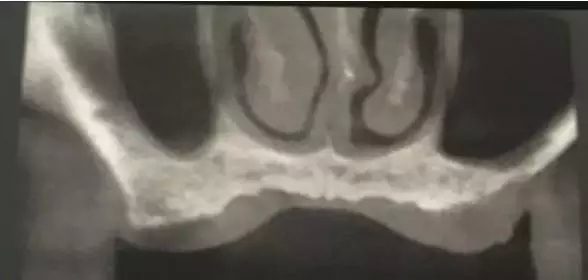

患者50歲,男性,身體健康。左上6,7缺失,骨高度2mm。

術(shù)前口內(nèi)照和CT片。

術(shù)后6,7牙位CT片,顯示充足的植骨量。